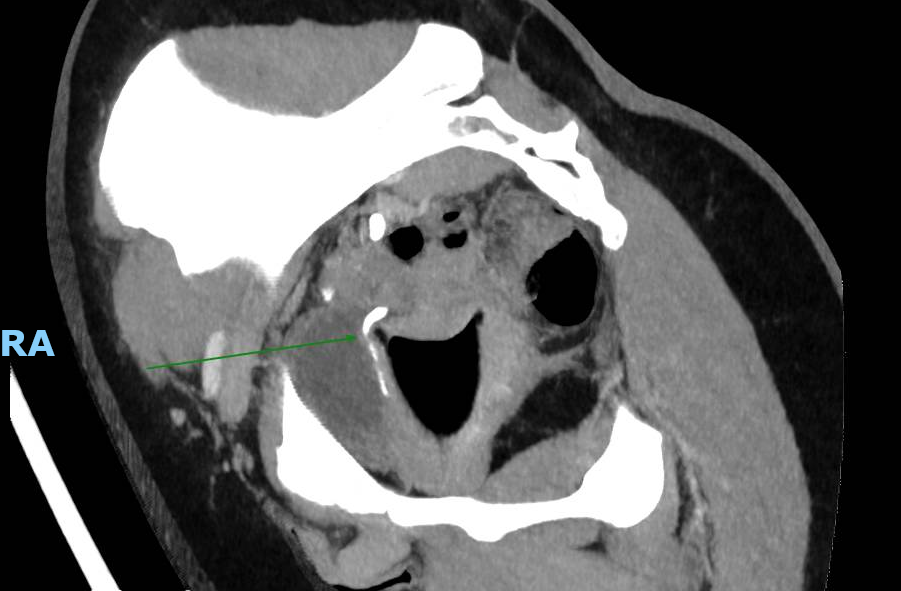

Le CT-scanner réalisé devant une colique néphrétique montre une compression urétérale droite extrinsèque sur une cup menstruelle. Cette dernière est retirée améliorant rapidement les douleurs.

Il existe 5 cas similaires publiés entre 2018 et 2020 (1), tous concernant l’uretère droit. Une étude ex-vivo comparant 14 marques de cup, de tailles et formes différents, a démontré qu’une cup trop grande ou trop rigide pouvait être la cause d’une compression des voies urinaires, en plus d’un inconfort (2).

Ce cas et la littérature qui y est liée démontre l’importance d’exclure la présence d’une cup en cas de colique néphrétique chez les femmes pré-ménopausées.